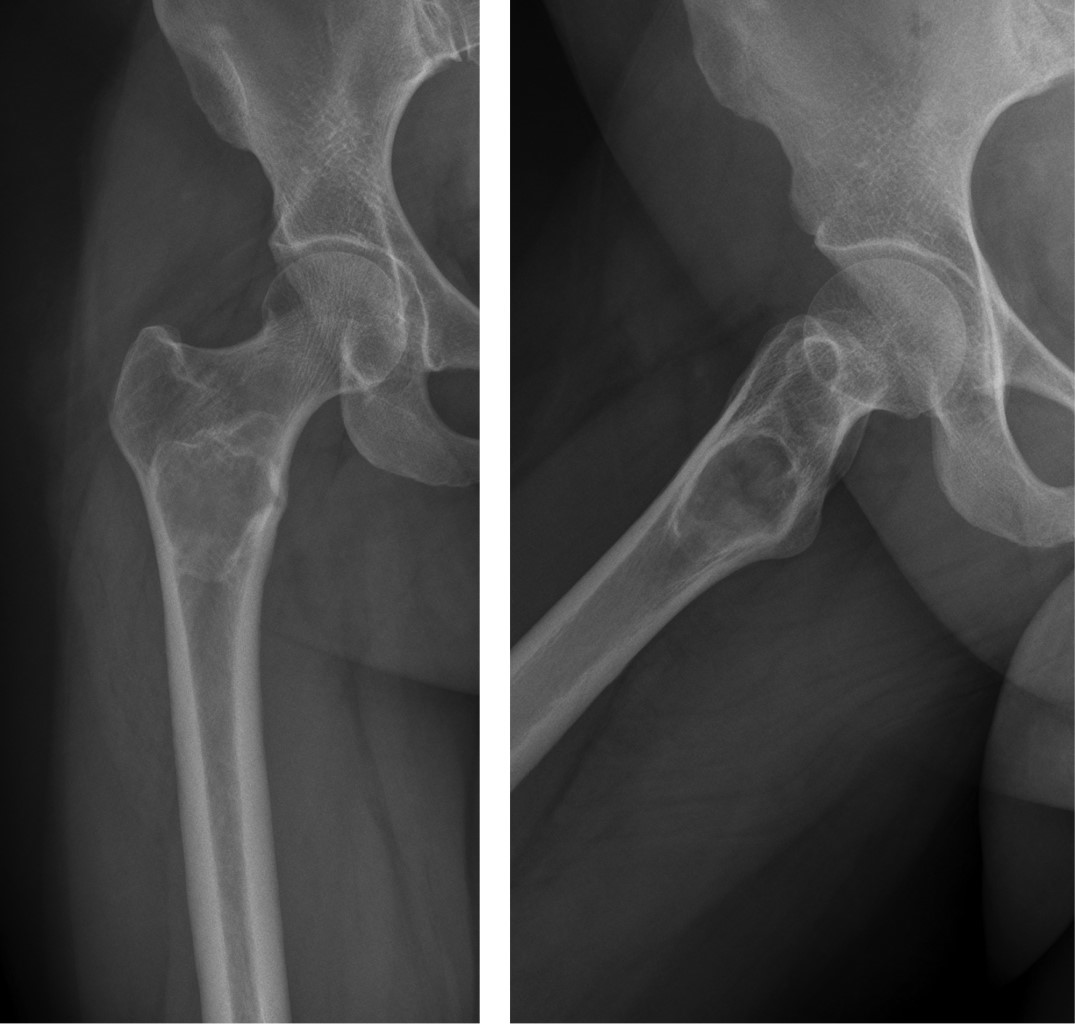

Liposclerosing myxofibroma of the proximal femur: diagnostic and therapeutic controversies. Apropos of 3 clinical cases

Introduction: The bone liposclerosing myxofibrous tumour (LSMFT) is a rare benign fibro-osseous tumor with characteristic clinical-radiological features, although its diagnosis and treatment are controversial. Material and methods: We present three patients, two women and one man, with a mean age of 46 years, diagnosed with LSMFT. The findings of the complementary imaging tests and the treatment performed are presented: observation in two patients and curettage, and the third patient was treated with curettage, grafting and surgical fixation. Results: The first two patients, after 10 and three years of follow-up, respectively, maintain the same symptoms and no progression of the lesion. Conclusions: The diagnosis of LSMFT can be assumed by clinical and imaging data without biopsy. In the absence of signs that suggest malignancy, observation is justified, limiting the surgical indication to symptomatic cases and/or those with risk of pathological fracture.

Figure 6

Figure 7